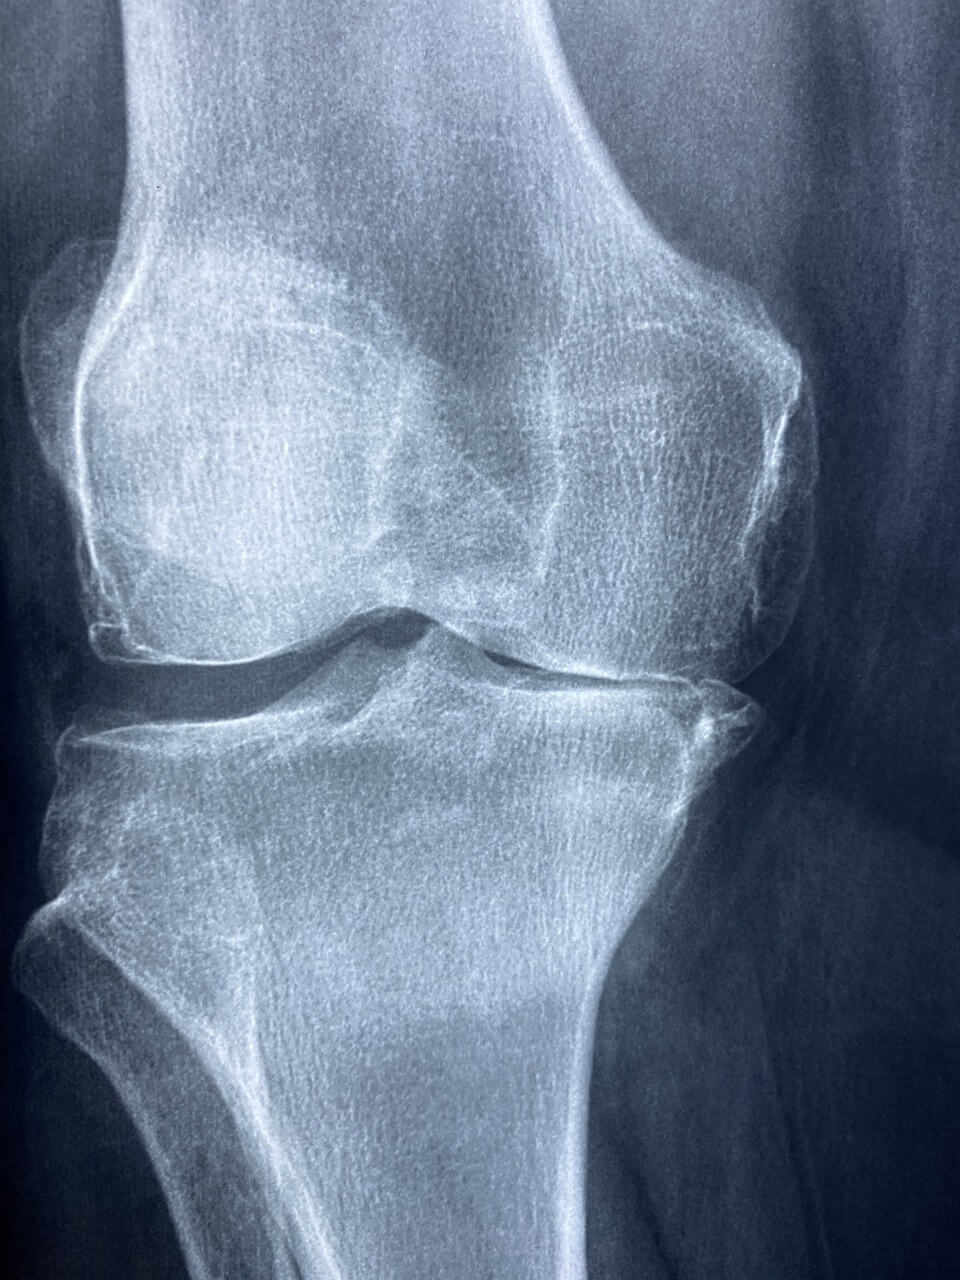

관절염 진단 및 치료방법

정형외과에서의 정밀 진단이 가장 우선입니다. 단순 통증일 수도 있지만, 연골 손상 정도를 파악해야 정확한 치료 방향이 나와요.